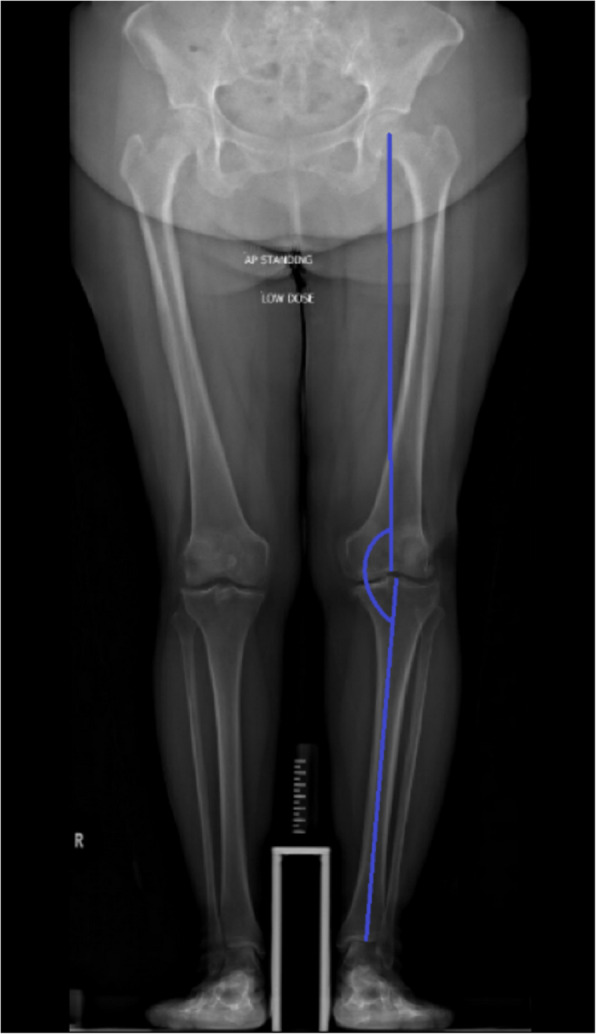

背景:本研究比较了无图像机器人辅助全膝关节置换术(RATKA)与基于加速度计的导航(ABN)系统在手术精度和早期临床结果方面的差异。方法:回顾性分析2017 - 2023年153例(178个膝关节)行原发性全膝关节置换术的患者。使用卡方检验、学生t检验和ANCOVA评估手术准确性和功能预后至术后12个月。还进行了基于患者人口统计学的亚组分析。结果:153例患者中101例行RATKA, 52例行ABN。RATKA显示出优越的对准精度,与计划对准的偏差显著降低(P结论:与ABN相比,RATKA提供了更高的精度,并改善了早期恢复,支持其作为TKA首选技术的潜力。其优化运动学对齐的能力可能有助于提高患者的预后。与ABN相比,RATKA提供了一个独特的优势,在计划对齐中实现了更高的准确性,这可能转化为改进的功能恢复。建议进行更大规模的进一步研究以证实这些发现。

Results: Among 153 patients, 101 underwent RATKA, and 52 received ABN. RATKA demonstrated superior alignment accuracy with a significantly lower deviation from the planned alignment (P < 0.05). Additionally, RATKA led to significantly better postoperative functional scores at 6 weeks (P = 0.001) and 3 months (P = 0.001), even after adjusting for preoperative functional differences.